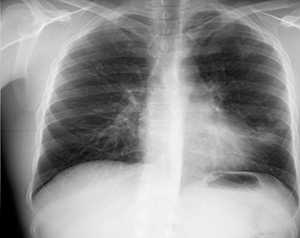

Пациент У., 1987 года рождения (на момент наложения ИП полных 28 лет). При контрольном рентгенологическом исследовании (через 3 месяца после ХТ) в S1-2 слева выявлена замкнутая кольцевидная тень диаметром 31 мм, томографически — в Д1 справа полость распада (см. рис. 2).

При исследовании мокроты на МБТ выявлен рост культуры МБТ, по результатам тестирования на лекарственную чувствительность (ТЛЧ) — МЛУ МБТ (HRS). Диагноз: кавернозный туберкулез верхней доли левого легкого, МБТ (+) плюс, МЛУ (HRS).

Пациенту предложен ИП. Получено согласие. Выполнена контрольная обзорная рентгенограмма органов грудной клетки и томографическое исследование — каверна в Д1 слева сохраняется (см. рис. 3).

Данное Z3≤1,07, прогнозируем длительность применения ИП в течение 3-х месяцев. ИП поддерживали на протяжении 3-х месяцев. Каверна закрылась (см. рис. 4).